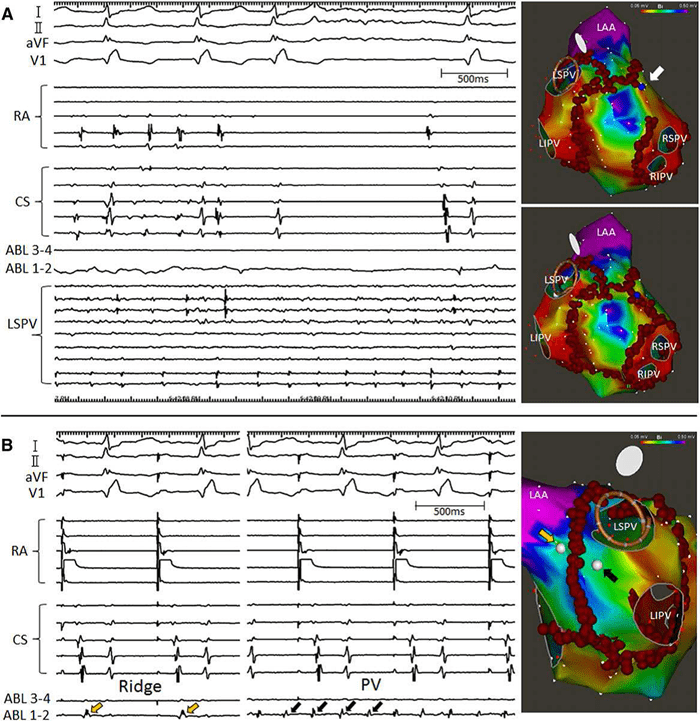

Voltage Mapping and AF Ablation Strategy

Panel B: The signals (EGMs) in the ablation catheter after restoration of normal sinus rhythm, showing that the AF inside the isolated left-sided PVs (black arrows) organized into the AT. EGMs outside the left-sided PVs showed the paced atrial signals (yellow arrows).